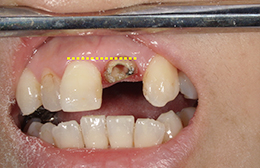

矯正による歯牙の挺出をエクストリュージョンといい、歯に持続的な力を加えることにより、健全歯質(虫歯に侵されていないところまで)を引っ張り出す方法(部分矯正)です。

歯茎の線に左右差がないので、外科的に埋まっている根っこ(歯根)を出してしまうと審美的問題が起きてしまいます。

週に1回程度、けん引するゴムを交換していきます。

外科的に被せ物を作るときに必要な健全歯質を作り出すことです。